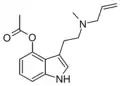

| MALT | artificial | H | CH3 | H2C=CH-CH2 | N-methyl-N-allyltryptamine | 1366416-29-6 |